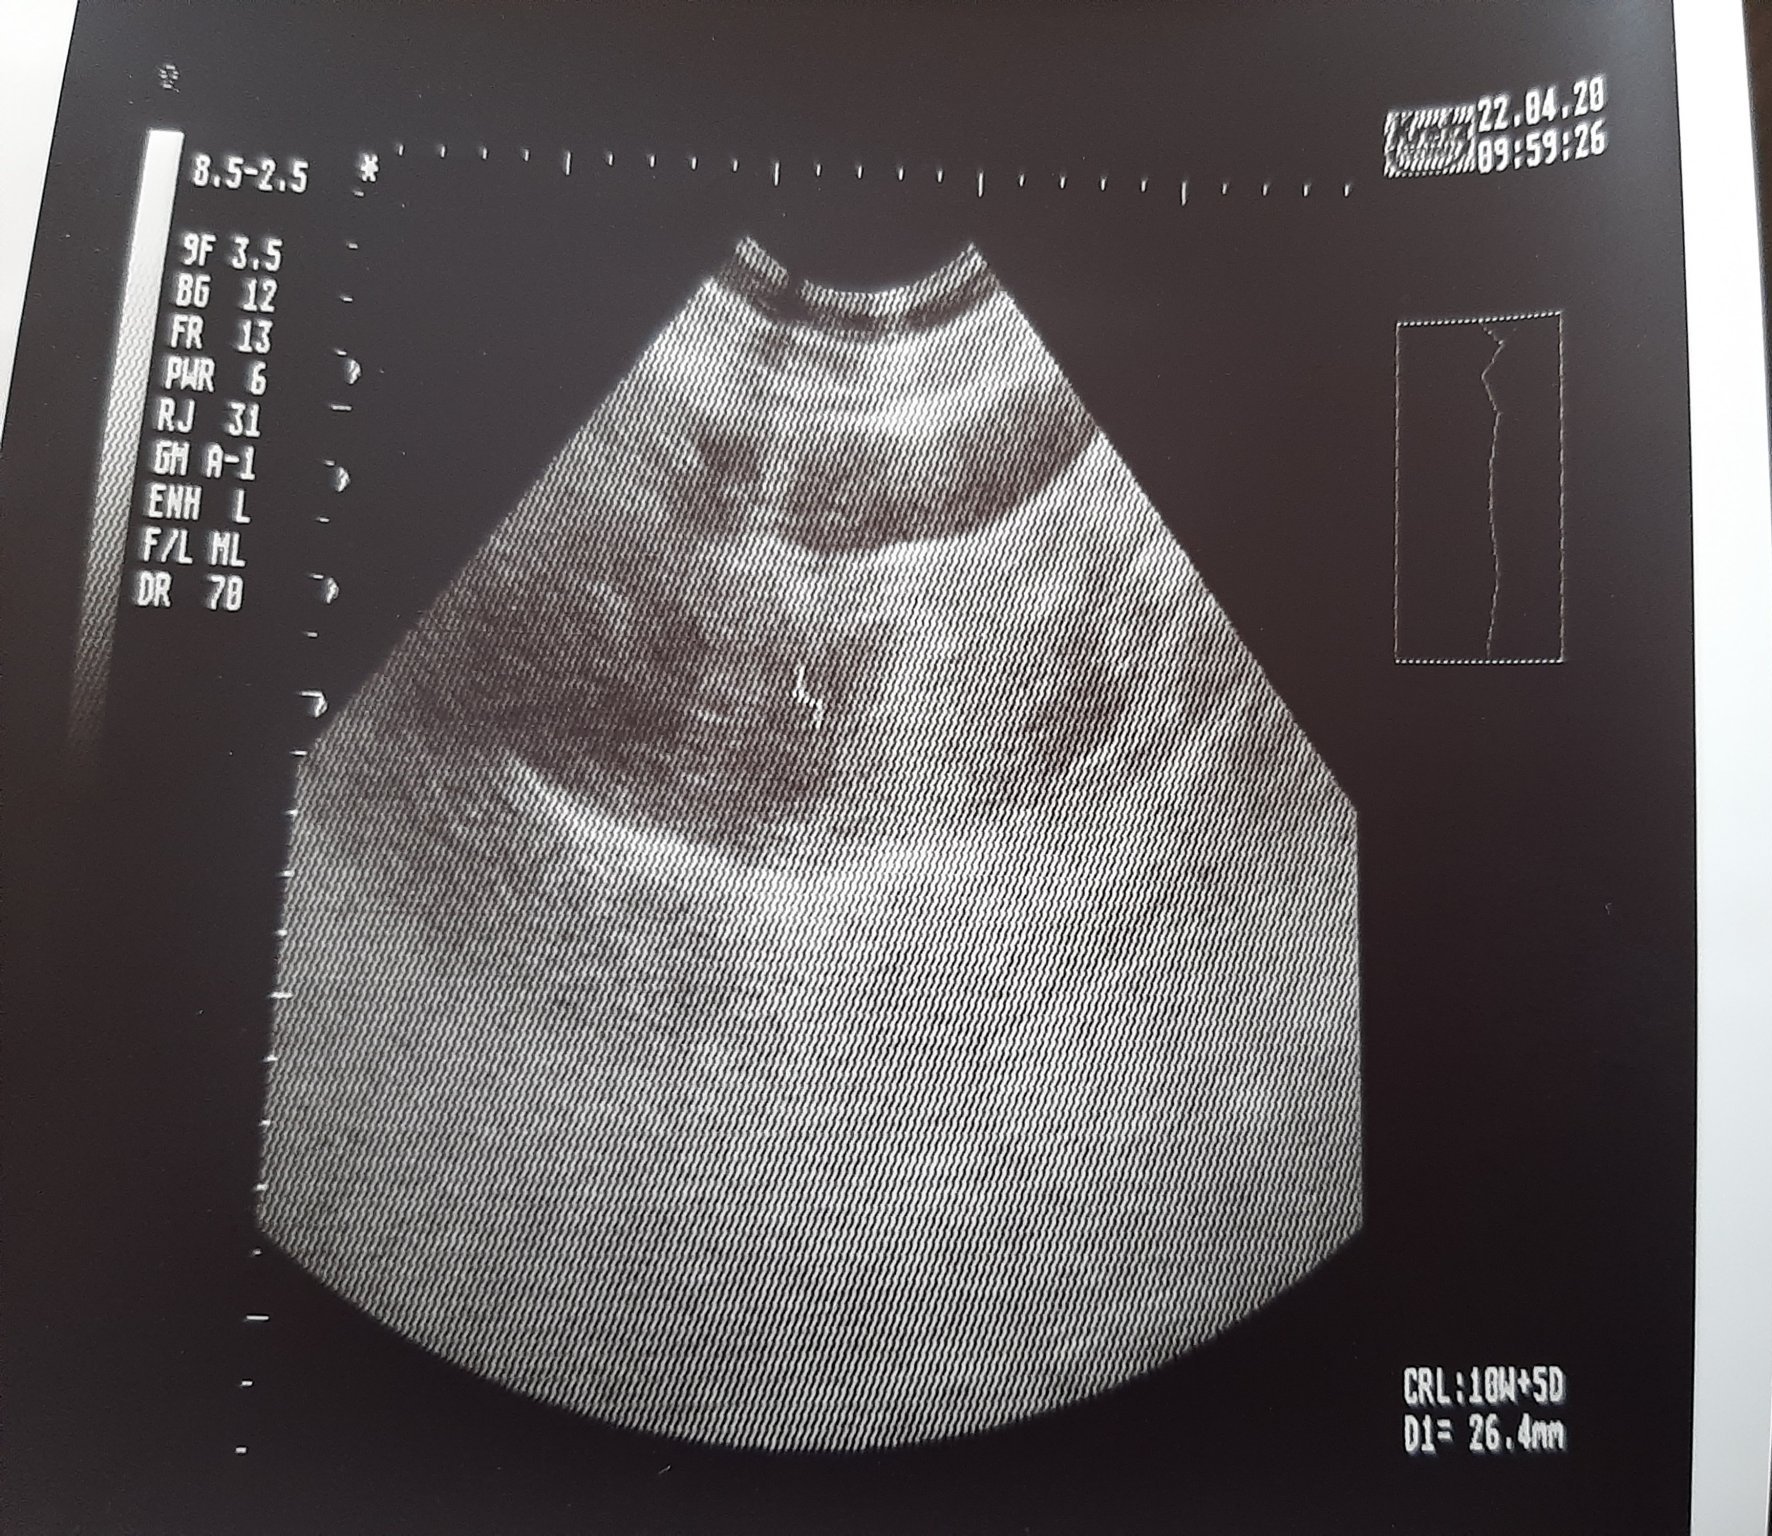

Момичета, това е снимката от ултразвука. Докторката каза че това тъмното петънце вдясно е мехурчето. Тези писаните неща по снимката не ги разбирам.

Аз от снимката разчетох само, че е 10с и 5 дни и е голямо 26.4 мм

Възвожно ли е да е 10с+5 дни при положение , ме приложенията ми показват 8 с+3дни ?

Тя ми каза че не отговаря на 9та седмица , но нищо друго

Infinity, къде си била на преглед? Качеството на снимката не е добро, а и не е достатъчно информативна... Кога беше датата на последната ти менструация? Колко ти е дълъг цикъла?

Последната менструация беше на 23.02 , 36 дне ми е цикъла. Ходих при една лекарка в ДКЦ в нашия град , само да вметна че снимката е от коремен ехограф. Със сигурност апаратурата е по-стара от тази на Щерев ( виждам, че твоите са от там) .